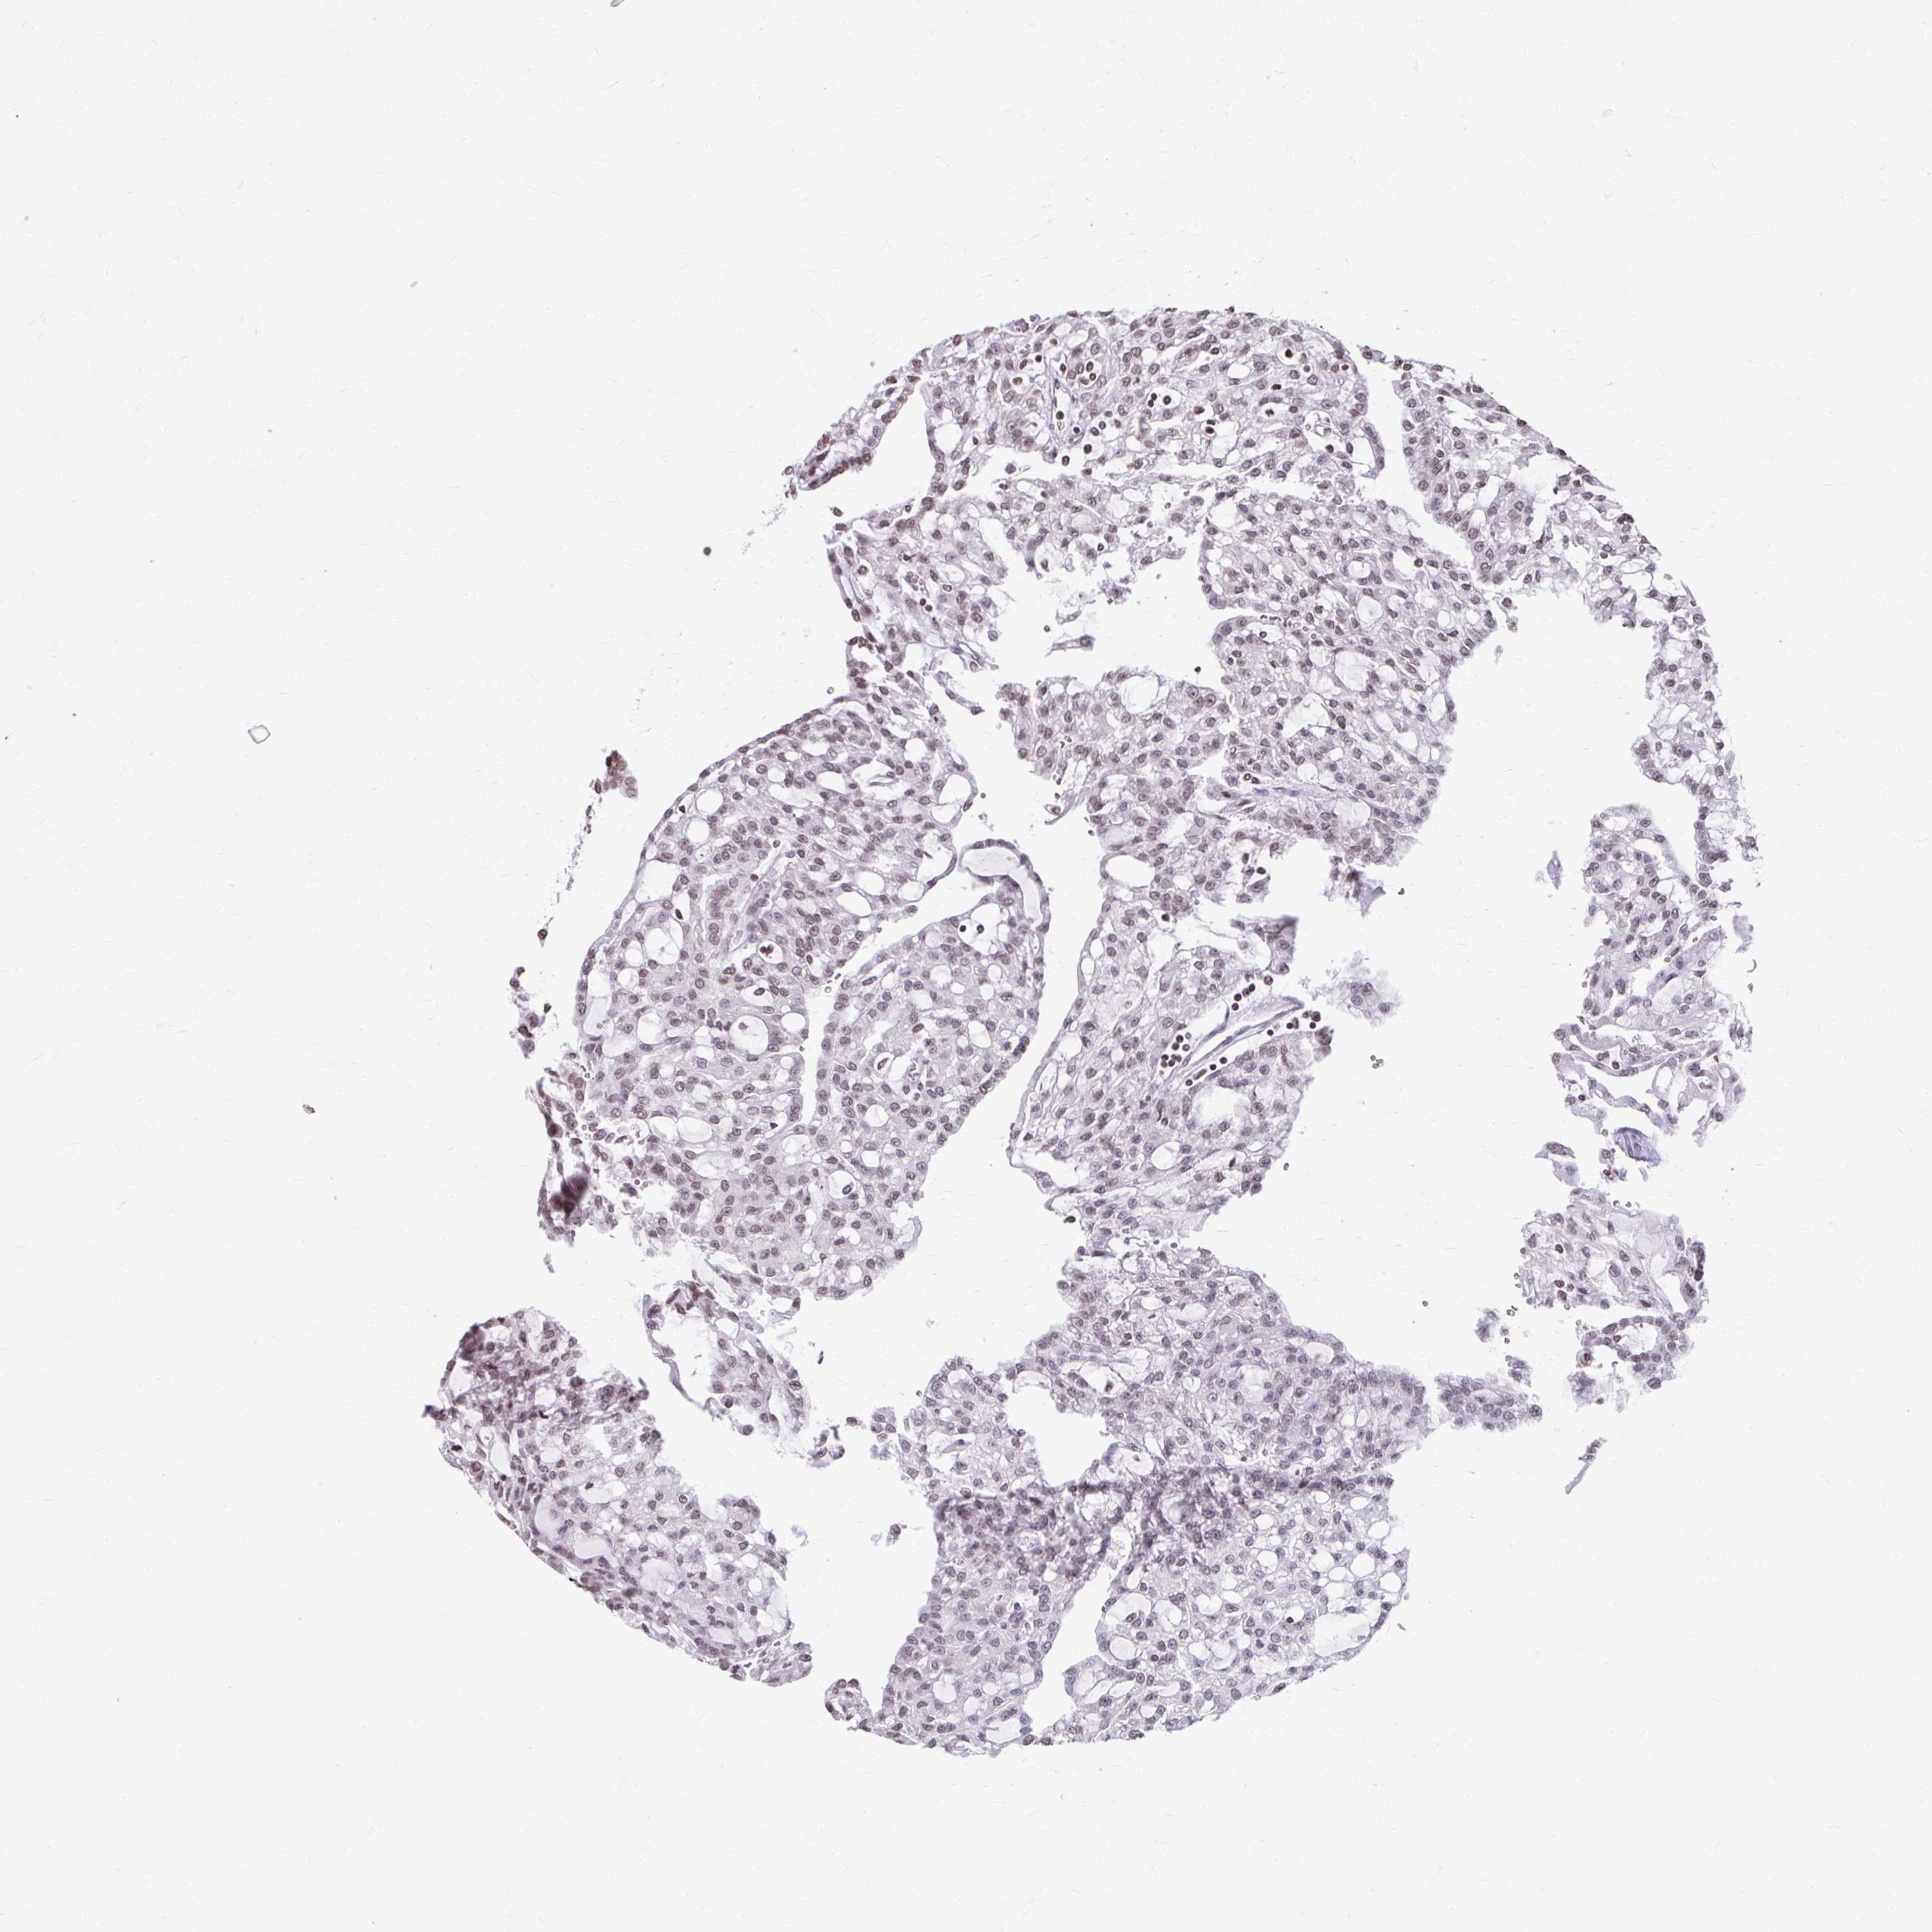

KIDNEY RENAL PAPILLARY CELL CARCINOMA (TCGA) - Interactive survival scatter ploti

The Survival Scatter plot shows the clinical status (i.e. dead or alive) for all individuals in the patient cohort, based on the same data that underlies the corresponding Kaplan-Meier plots. Patients that are alive at last time for follow-up are shown in blue and patients who have died during the study are shown in red.

The x-axis shows the expression levels (FPKM) of the investigated gene in the tumor tissue at the time of diagnosis. The y-axis shows the follow-up time after diagnosis (years). Both axes are complimented with kernel density curves demonstrating the data density over the axes. The top density plot shows the expression levels (FPKM) distribution among dead (red) and alive patients (blue). The right density plot shows the data density of the survived years of dead patients with high and low expression levels respectively, stratified using the cutoff indicated by the vertical dashed line through the Survival Scatter plot. This cutoff is automatically defined based on the FPKM cutoff that minimizes the p-score. The cutoff can be changed by dragging the vertical line or by entering a cutoff value in the square labeled "Current cut-off".

Under the Survival Scatter plot the p-score landscape (black curve; left axis) is shown together with dead median separation (red curve; right axis). Dead median separation is the difference in median mRNA expression between patients who have died with high and low expression, respectively. It is calculated as follows: median FPKM expression of dead patients with high expression - median FPKM expression of dead patients with low expression. This is intended to aid the user in visually exploring custom cutoffs and the associated p-scores and dead median separation.

Individual patient data is displayed and can be filtered by clicking on one or more of the category buttons on the top of the page. Categories describing expression level and patient information include: high, low, alive, dead, female, male and tumor stages. The scale of the x-axis can be toggled between linear and log-scale by clicking on the "x log" button. Mouse-over function shows TCGA ID, patient information and mRNA expression (FPKM) for each patient.

& Survival analysisi

Kaplan-Meier plots summarize results from analysis of correlation between mRNA expression level and patient survival. Patients were divided based on level of expression into one of the two groups "low" (under cut off) or "high" (over cut off). X-axis shows time for survival (years) and y-axis shows the probability of survival, where 1.0 corresponds to 100 percent.

ORC3 is not prognostic in Kidney Renal Papillary Cell Carcinoma (TCGA)

Best expression cut offi

Based on the FPKM value of each gene, patients were classified into two groups and association between prognosis (survival) and gene expression (FPKM) was examined. The best expression cut-off refers the FPKM value that yields maximal difference with regard to survival between the two groups at the lowest log-rank P-value. Best expression cut-off was selected based on survival analysis .